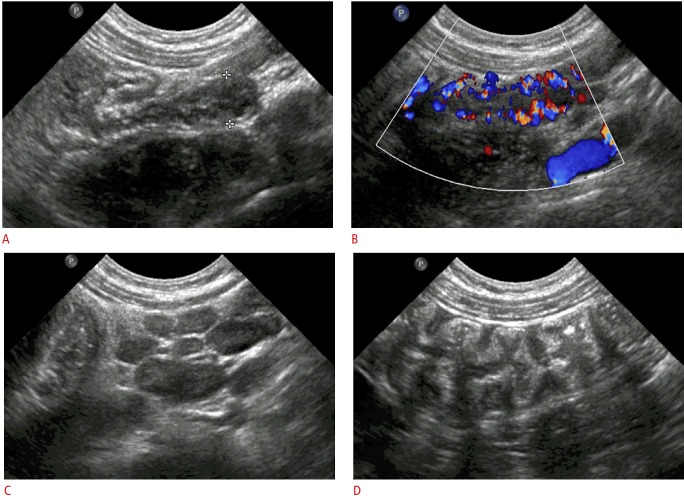

Fig. 5. A 3-year-old boy with secondary appendicitis.

The laboratory findings showed an elevated serum C-reactive protein level (13.8 mg/L). A. Gray-scale ultrasonography (an appendiceal longitudinal scan) shows an increased maximal outer diameter of the appendix of 7.8 mm with wall thickening and no periappendiceal fat inflammation. B. Color Doppler ultrasonography shows mural hyperemia of the appendix. C. Multiple enlarged lymph nodes are seen in the right lower quadrant of the abdomen, representing mesenteric lymphadenopathy. D. Marked wall thickening of the ascending colon is noted. The patient was diagnosed with ileocolitis and secondary appendicitis. He was treated with conservative management and the follow-up ultrasound showed normalization of the appendix.